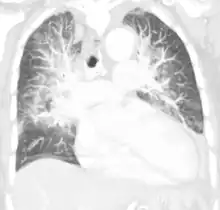

Pulmonary edema on CT-scan (coronal MPR)

Low oxygen saturation in blood and disturbed arterial blood gas readings support the proposed diagnosis by suggesting a pulmonary shunt. A chest X-ray will show fluid in the alveolar walls, Kerley B lines, increased vascular shadowing in a classical batwing peri-hilum pattern, upper lobe diversion (biased blood flow to the superior parts instead of inferior parts of the lung), and possibly pleural effusions. In contrast, patchy alveolar infiltrates are more typically associated with noncardiogenic edema[2]